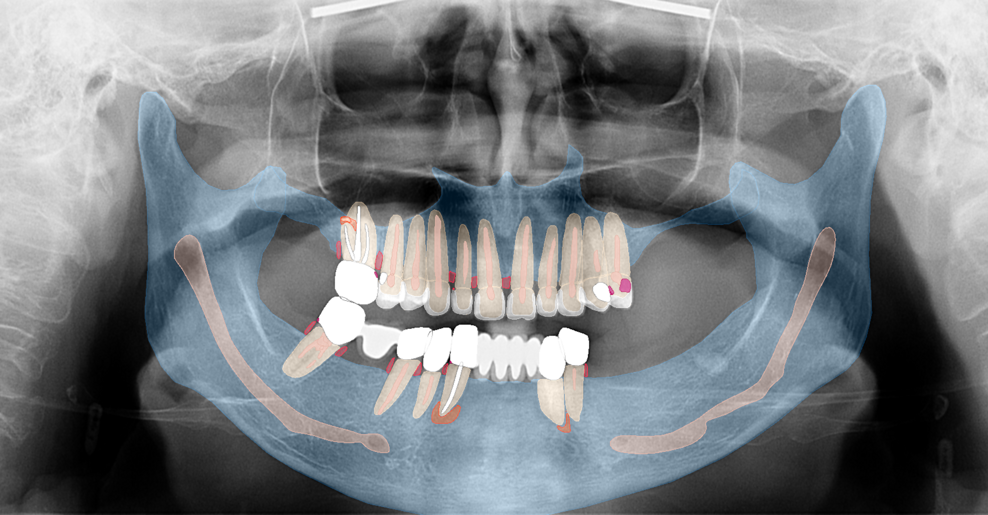

Fig. 1a: Pre-op panoramic radiograph. (All images: Dr Ádám Kapai, Dr Tamás Chikány, Tamás Csornai)

Fig. b: Pre-op panoramic radiograph and the findings.

Intra-oral examination revealed compromised mandibular dentition, an old fixed prothesis, missing posterior teeth on the left side, periodontal involvement and gingival inflammation. A panoramic radiograph was obtained, and the findings were reported to the patient (Figs. 1a & b; 2a & b). Both mandibular canines had visible periapical radiolucencies. A CBCT scan was performed for a more detailed assessment of the alveolar bone anatomy (Figs. 3a & b). Temporomandibular joint examination revealed no indication of dysfunction (crepitus, clicking or pain).